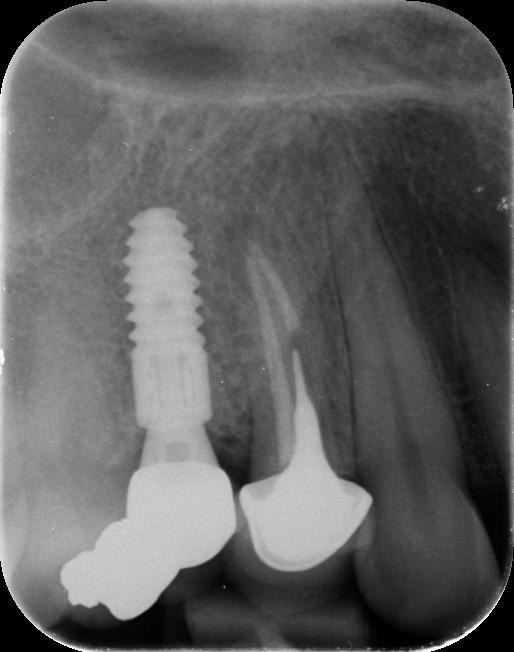

13. What option can be selected regarding the implants seen in this X ray?